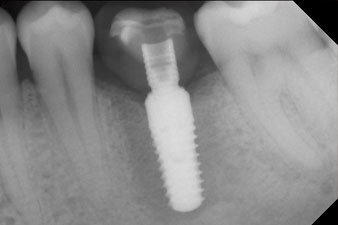

Das Drehmoment beim maschinellen Einbringen war 43 Ncm. Zusätzlich wurde, nach Einschrauben eines speziellen, auf das Implantatsystem abgestimmten Mess-Pfostens (SmartPeg), der ISQ-Wert mit der Sonde des W&H Osstell ISQ Modul bestimmt.

Dieses Modul ist für das Implantmed von W&H optional erhältlich und wird an den Implantologiemotor gedockt (vgl. Abb. 11). Der dimensionslose ISQ-Wert war direkt bei der Insertion 64 in oro-vestibulärer und 68 in mesio-distaler Richtung (Maximalwert = 100). Dies hätte eine offene Einheilung oder sogar Sofortversorgung erlaubt.

Nach Abheilung der Weichgewebe wurde vor der weiteren prothetischen Versorgung die Implantatstabilität erneut bestimmt.

Beide Werte waren praktisch unverändert und lagen im Übergang vom mittleren in den hohen Bereich – wobei der niedrigere Wert immer als therapiebestimmende Referenz dient.

Damit konnten eine erfolgreiche Osseointegration und ausreichende biologische Stabilität dokumentiert werden, die eine Abformung in derselben Sitzung erlaubte.

Die Abschlussbilder zeigen die verschraubte monolithische Kompositkrone in situ und die Röntgenkontrolle (Abb. 9 und 10) (6).